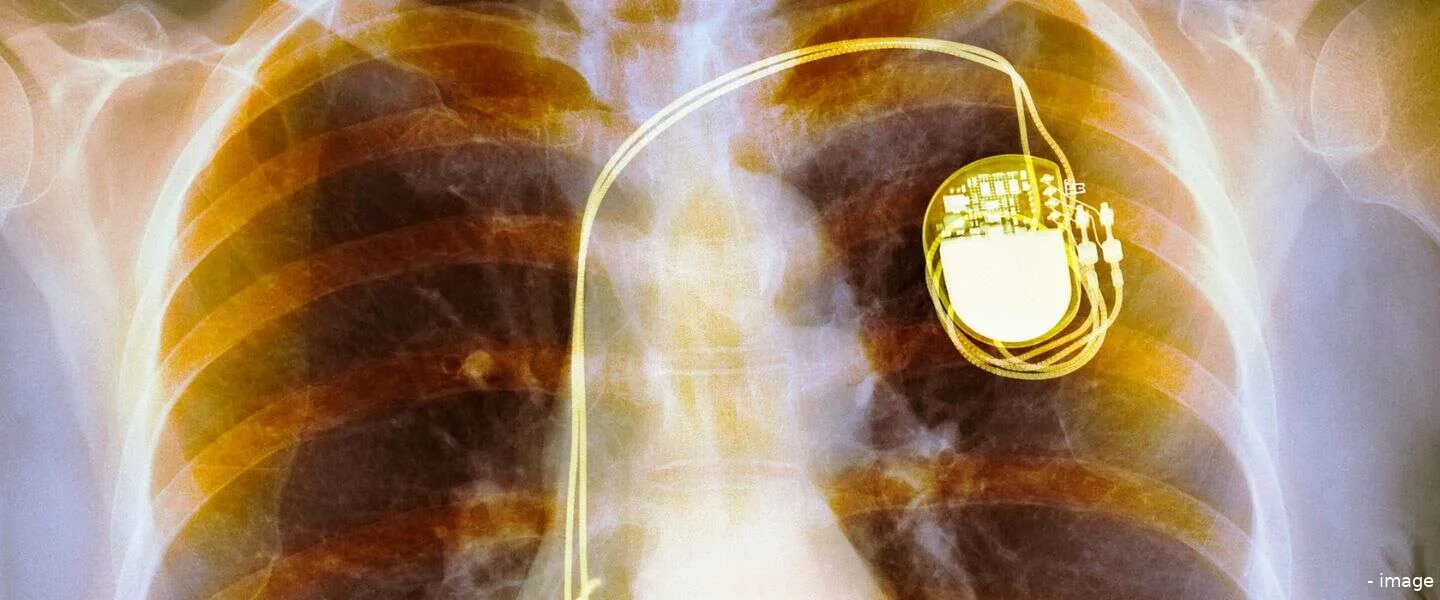

Als je een pacemaker hebt, dan ben je niet na één operatie klaar. Je moet regelmatig opnieuw onder het mes, namelijk om de batterij van het essentiële apparaat te vervangen. Daar komt in de toekomst mogelijk verandering in, want er is nu een batterij ontwikkeld die stabiele stroom opwekt in je eigen lichaam.

De batterij van een pacemaker gaat vijf tot tien jaar mee, maar daar zou bij dezen dus een oplossing voor kunnen zijn. Dat scheelt drukte op de OK en vooral is het een stuk veiliger en prettiger voor de patiënt.